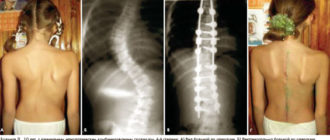

Последствия дисплазии тазобедренных суставов у детей Многие папы и мамы детей первого года жизни

Соха вальга тазобедренного сустава у детей что это Многие годы пытаетесь вылечить СУСТАВЫ? Глава